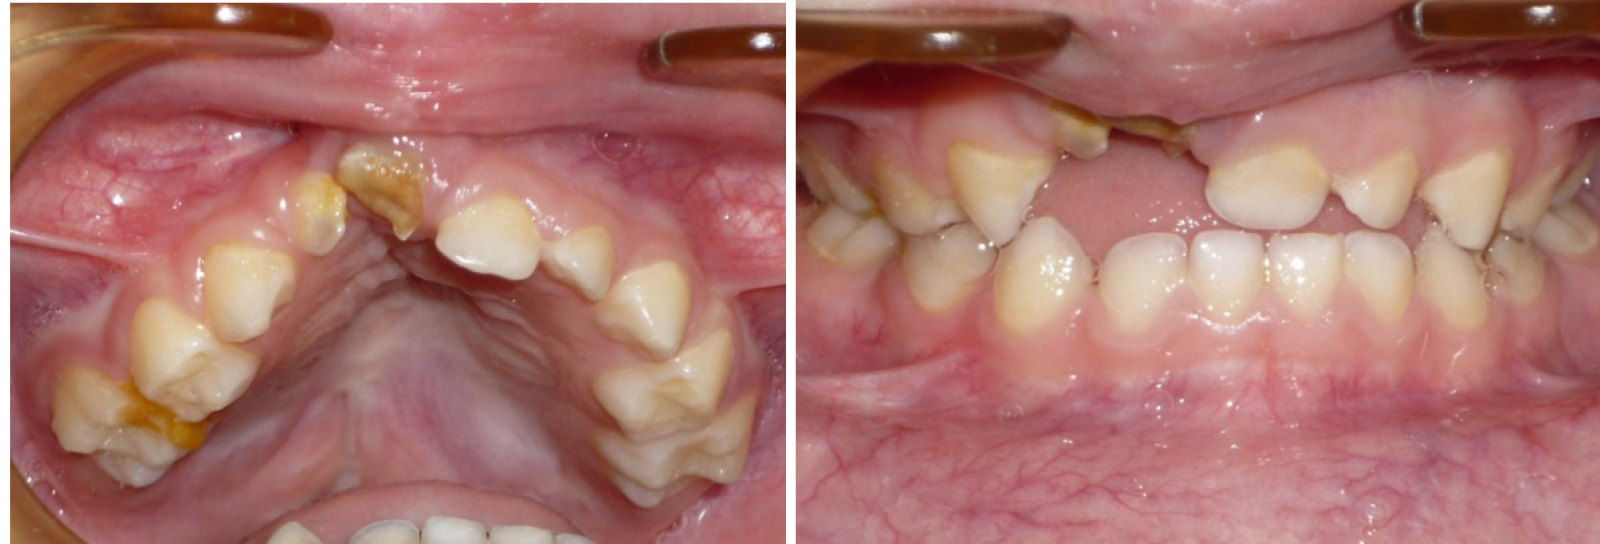

Эффективность предложенных методов графического построения прогнозируемых форм зубных арок определялась при анализе результатов лечения детей с врожденной аномалией в периоде молочного прикуса. С этой целью проведено лечение 15 детей с врожденным односторонним несращением губы и нёба. Практически во всех клинических случаях определялось сужение трансверсальных размеров, более выраженное в переднем сегменте арки. Окклюзия не соответствовала признакам физиологической нормы. Отмечалось укорочение глубины арки (рис. 2).

Лечение проводилось с применением несъемной дуговой аппаратуры. Фиксирующими элементами служили тонкостенные коронки (кольца) с припаянными вестибулярными брекетами. Размер металлической дуги определяли с помощью предложенных методов графического анализа (рис. 3). Металлические дуги меняли с учетом протокола лечения эджуайс-техникой до нормализации формы арки, соответствующей прогнозируемым размерам. После нормализации окклюзионных взаимоотношений аппарат использовался в качестве ретенционного до смены молочных зубов постоянными (рис. 4).